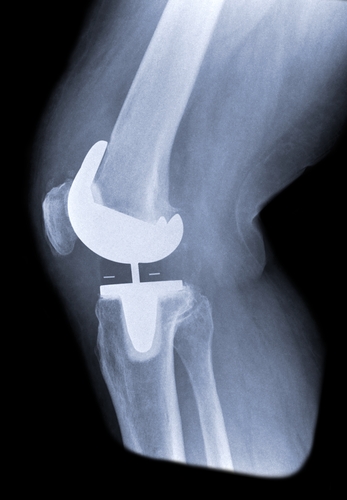

La mise en place de prothèses de genou (PTG) n’est pas rare, ayant atteint 113 600 actes en France en 2018, un chiffre appelé à augmenter de 33 % d’ici 2050. Cependant, la notion de succès est différente selon que l’on se place du côté du chirurgien (bénéfice mécanique) ou du patient (disparition de la douleur, du gonflement, de la gêne). Or, 10 à 34 % des patients présentent une douleur chronique post-PTG, les douleurs demeurant inexpliquées dans 20 % des cas et une reprise de prothèse sans cause identifiable se produit dans 9 % des cas en Angleterre.

Pour établir le diagnostic d’une douleur post-PTG, la radiographie et/ou l’échographie sont les premiers examens à réaliser. S’ils reviennent négatifs, il faudra demander une scintigraphie, idéalement au technétium, qui n’est cependant pas fiable durant la première année postopératoire ; le scanner permet de visualiser les malpositions et surdimensions.